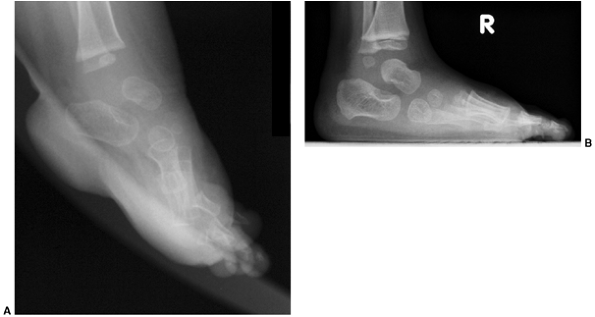

![]() |

Figure 30.14 A: Valgus deformity of the hindfoot is a complication of clubfoot management resulting in weak push-off and pain. B: Computed tomography (CT) scan is used to evaluate the deformity and the subtalar joint.

for rigid forefoot supination that may drive the hindfoot deformity.

anteroposterior and lateral radiographs of the foot underestimate the

deformity of hindfoot valgus in general. A CT scan will allow

evaluation of the subtalar joint as well as the alignment of the

hindfoot deformity. Also, be aware that valgus may result from the

tilting of the distal tibial articular surface.

calcaneal translational osteotomy as well as calcaneal lengthening, and

subtalar joint must be present and is best evaluated using a CT scan (Fig. 30.14B).